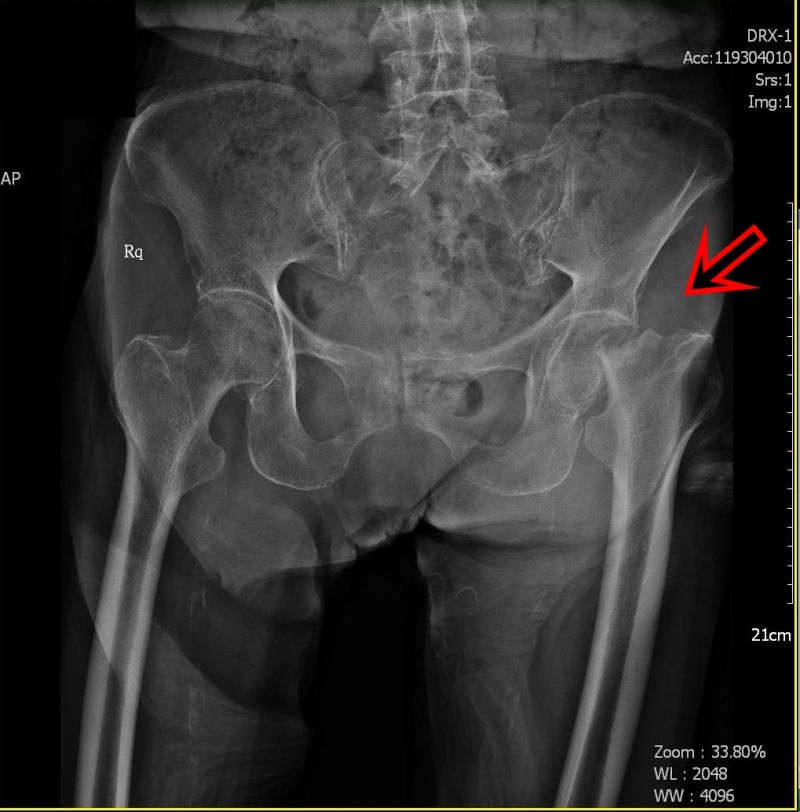

百歲嬤換關節,照樣趴趴走!101歲的陳卓阿嬤,身體一向硬朗,日前在家中不慎跌倒,當下痛到無法起身行走,經骨科X光檢查後,確診左側股骨頸骨折,立即進行半髖人工關節置換手術,住院一周即返家休養,目前行走自如。

收治病人的童綜合醫院骨科醫師徐自良表示,股骨頸是在髖部承接著大腿骨骨幹與髖關節股骨頭的樞紐,股骨頸骨折常發生於老年人,因為老年人股骨頸骨質疏鬆脆弱,就算是遭到不大的外力衝擊,都可能引起骨折。

徐自良指出,髖關節是股骨頭和髖臼的結合,就像一顆球嵌進一凹形窩,因為這種特殊的構造,使髖關節具有先天的穩定性,無須特殊的支持性韌帶,一旦發生股骨頸骨折時,需要使用人工的半髖關節來置換損壞的關節。